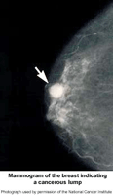

Mammography cannot prove that an abnormal area is cancer, but if it raises a significant suspicion of cancer, further investigation with ultrasound may be needed, and / or tissue will be removed for a biopsy. Tissue may be removed by needle or open surgical biopsy and examined under a microscope to determine if it is cancer.

Breast Cancer